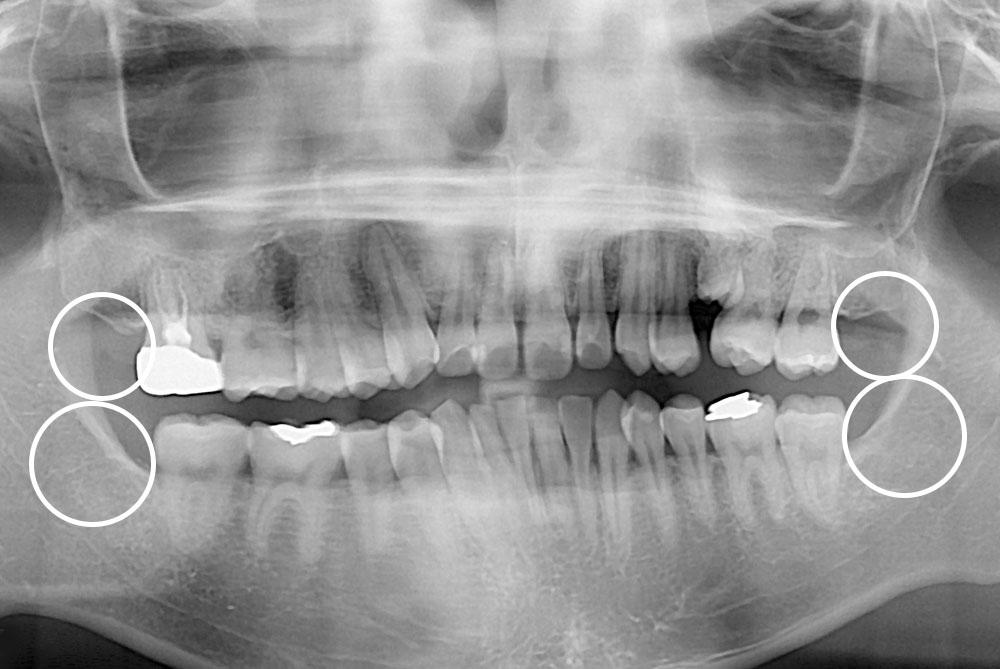

[사랑니] 매복 사랑니 발치

치료전 : 2019-04-12

치료후 : 2020-03-05

세종치과는 구강악안면외과학 박사이신 원장님이 발치하는 치과입니다.